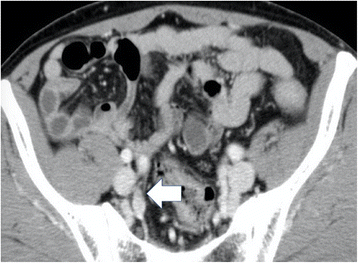

Six months after the operation, however, the patient’s serum CEA levels increased to 7.0 ng/mL. Abdominal CT revealed swollen lymph nodes in the right common and internal iliac artery area (Fig. 3a, b). Positron emission tomography (PET) with CT revealed hot spots (SUVmax, 5.3) in the same lesions (Fig. 4a, b). No other metastases were observed. Accordingly, we retrospectively re-evaluated the preoperative CT images. Although we detected no apparent swollen lymph nodes, we observed an unusual soft tissue area around the right internal iliac artery (Fig. 5). The preoperative diagnosis was an LLN metastasis localized in the right pelvic area, and an open unilateral LLN dissection of the right common iliac, internal iliac, and obturator nodes was performed. The branches of the right internal iliac vessels, including the superior vesical and obturator vessels, were ligated and divided at their origins with resected lymph nodes; however, the internal iliac artery and pelvic nerve plexus were preserved. Histologically, 15 lymph nodes were resected; of these, 3 (2 in the proximal internal iliac node and 1 in the common iliac node) contained metastases of adenocarcinoma (Fig. 2d). The postoperative course was uneventful. The patient was given 12 cycles of adjuvant chemotherapy with FOLFOX (fluorouracil, leucovorin, and oxaliplatin). He remains healthy without signs of recurrence at 30 months after the second surgery.

In general, enhanced CT is used as a preoperative imaging tool for rectal cancer. Currently, the European Society for Medical Oncology guidelines recommend pelvic magnetic resonance imaging (MRI) for the initial staging of rectal cancer because this modality is highly accurate for determining localization, clinical T and N stages, and potential circumferential resection margins [1]. The diagnostic sensitivity and specificity of MRI for lymph node metastasis are 77 and 71%, respectively [12]. Additionally, the usefulness of diffusion-weighted imaging (DWI)-MRI has recently been reported [13,14,15]. The accuracy of DWI-MRI is better than that of both CT and 18FDG-PET (86.6 vs. 76.0% and 78.3 vs. 69.9%, respectively) [14, 15]. In our case, we considered the patient to be metastasis-negative, based on enhanced CT findings. The LLN metastasis was revealed only 6 months after the initial surgery, when an unusual soft tissue area around the right internal iliac artery was retrospectively detected on preoperative CT images. Based on these two factors, it is possible that the LLN metastasis existed at the time of initial surgery and could have been diagnosed by DWI-MRI.